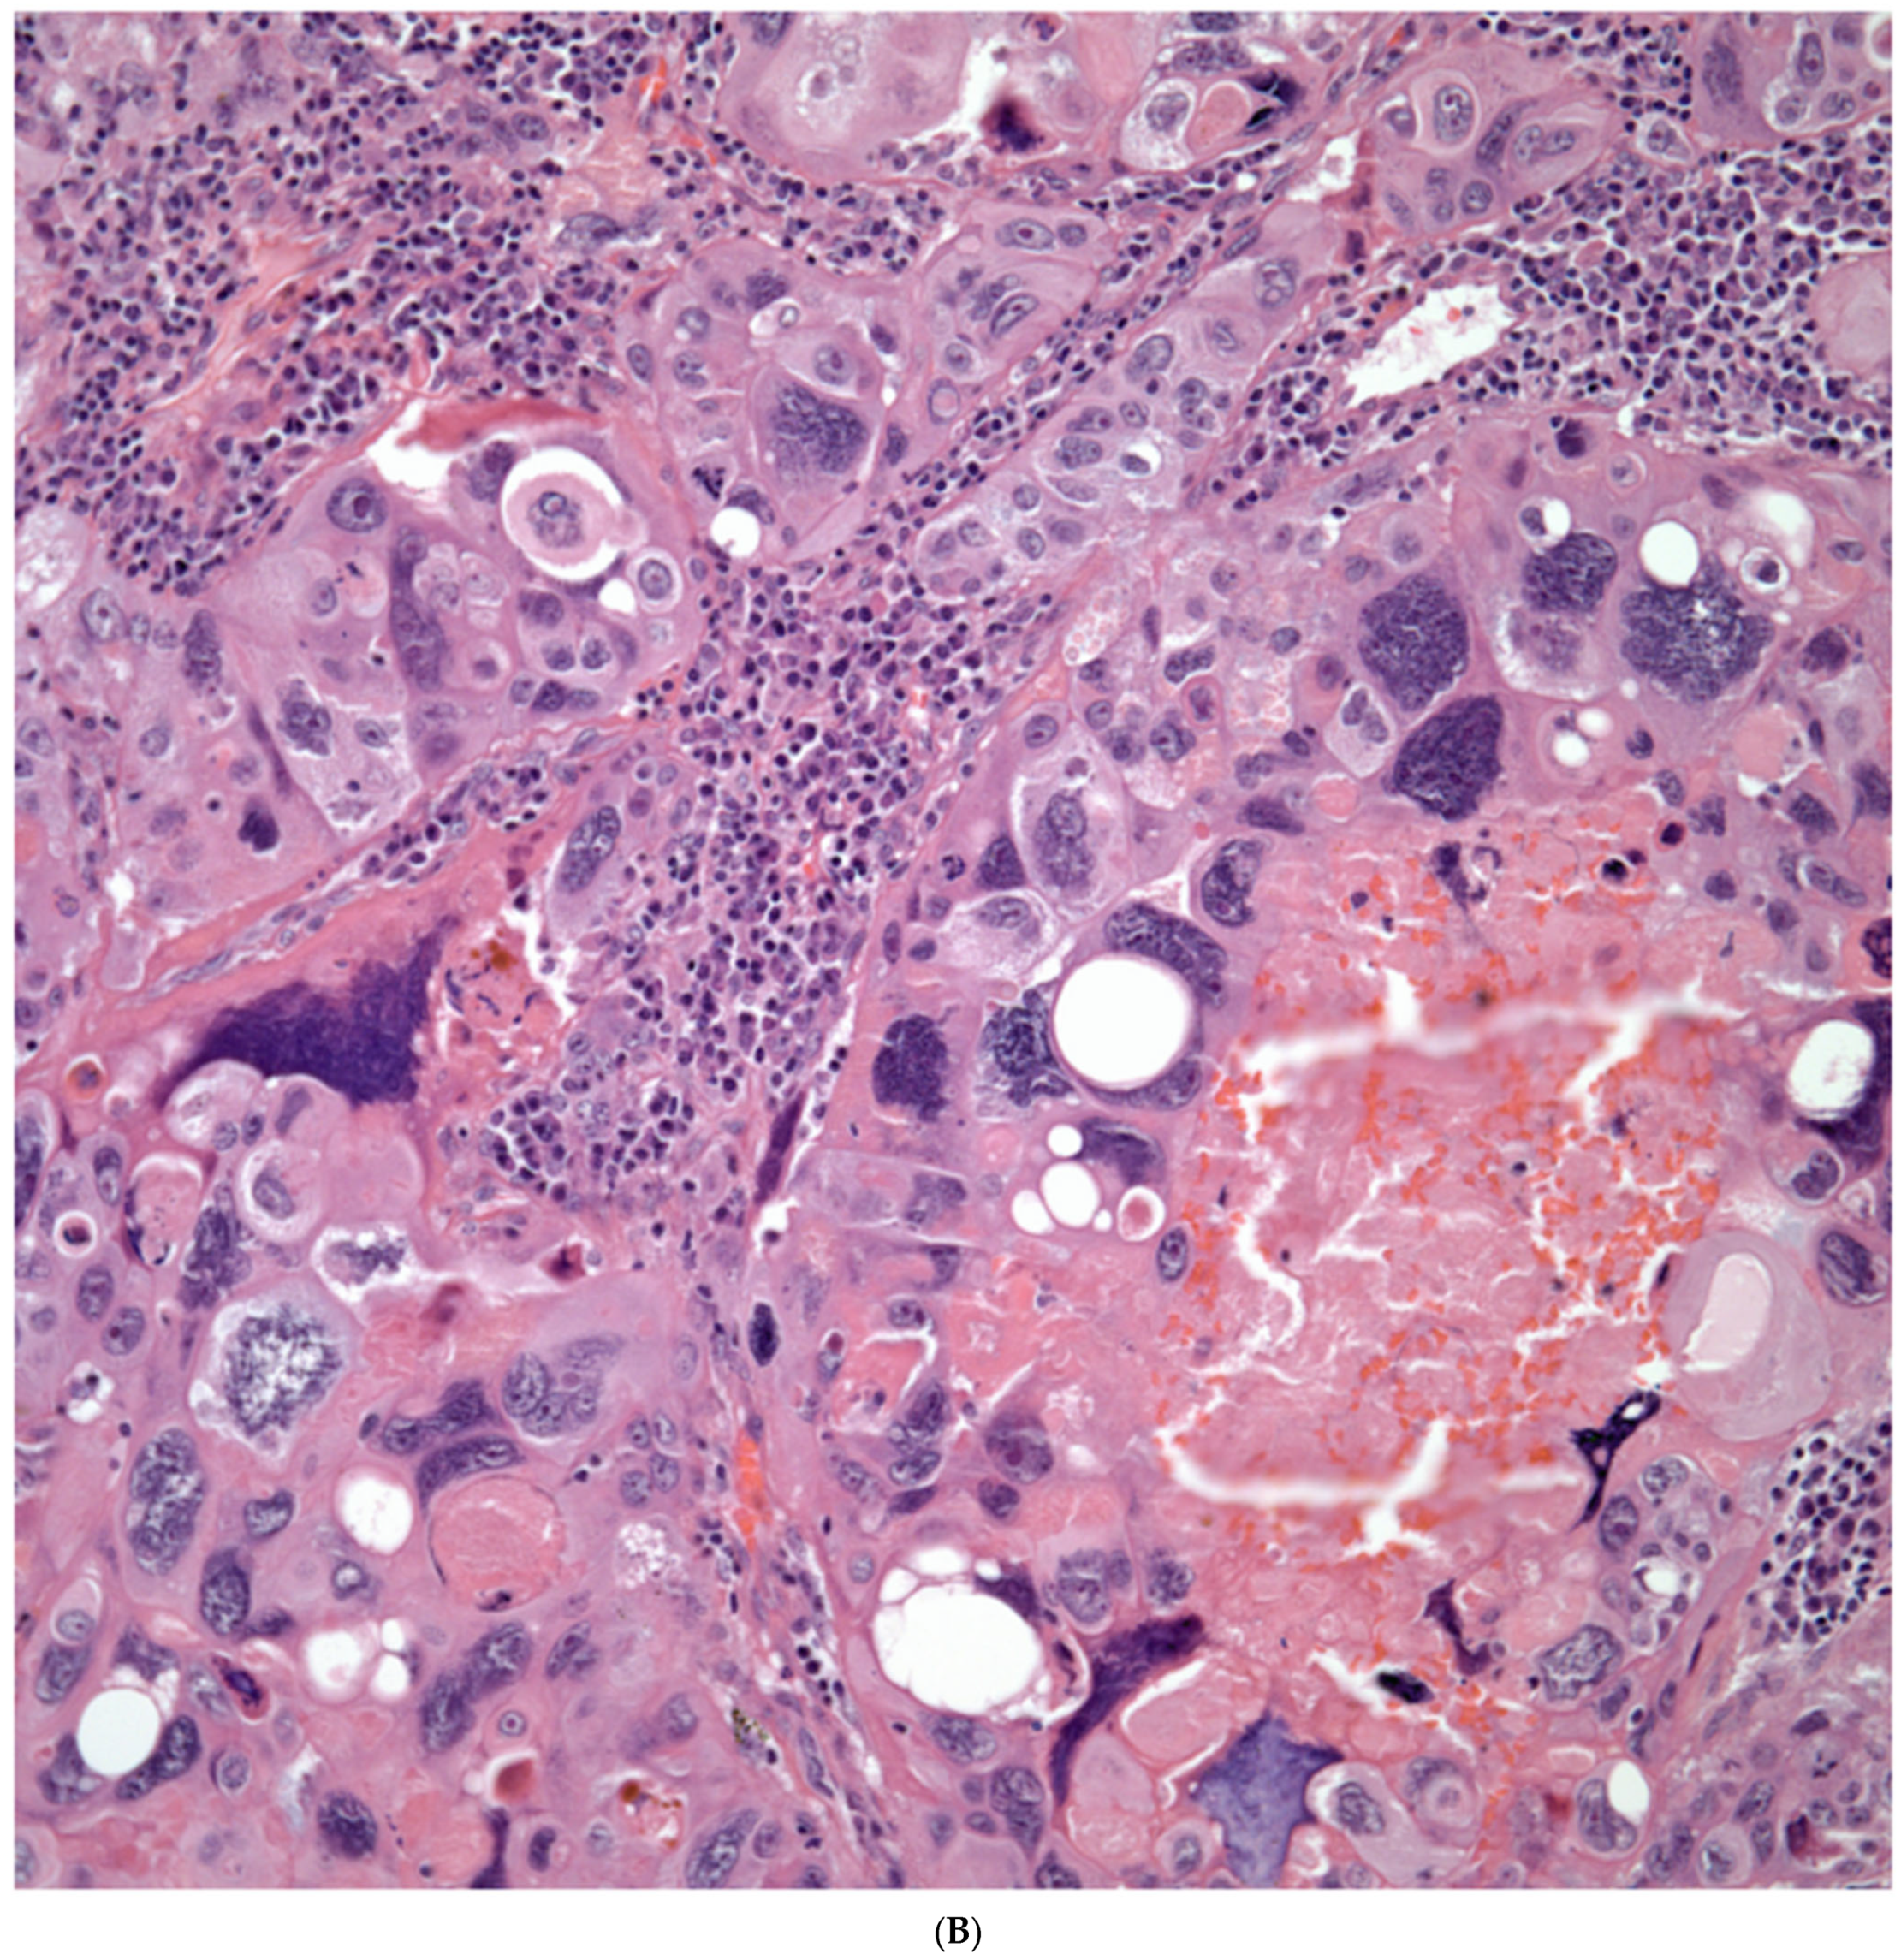

Giant Cell Carcinomas: These tumors may show predominantly a neoplastic cellular proliferation composed exclusively of multinucleated giant cells or a predominantly giant cell carcinoma (Figure 5A,B) or associated with a conventional non-small cell carcinoma like adenocarcinoma or squamous cell carcinoma. The giant cell carcinoma may show giant cells of the syncytiotrophoblastic, osteoclastic, or null cell type. The giant cell carcinomas of the null cell type characteristically show a prominent inflammatory background and giant cells engulfing inflammatory cells (emperipolesis) (Figure 6A,B). The tumors composed of osteoclast-like giant cells show giant cells like those described in bone tumors (Figure 7A,B).

Figure 5.

(A) Predominantly giant cell carcinoma; (B) Marked atypia and numerous multinucleated malignant giant cells.

Figure 6.

(A) Giant cell carcinoma, null cell type, note the inflammatory background; (B) Malignant giant cells with inflammatory cells and focal emperipolesis.